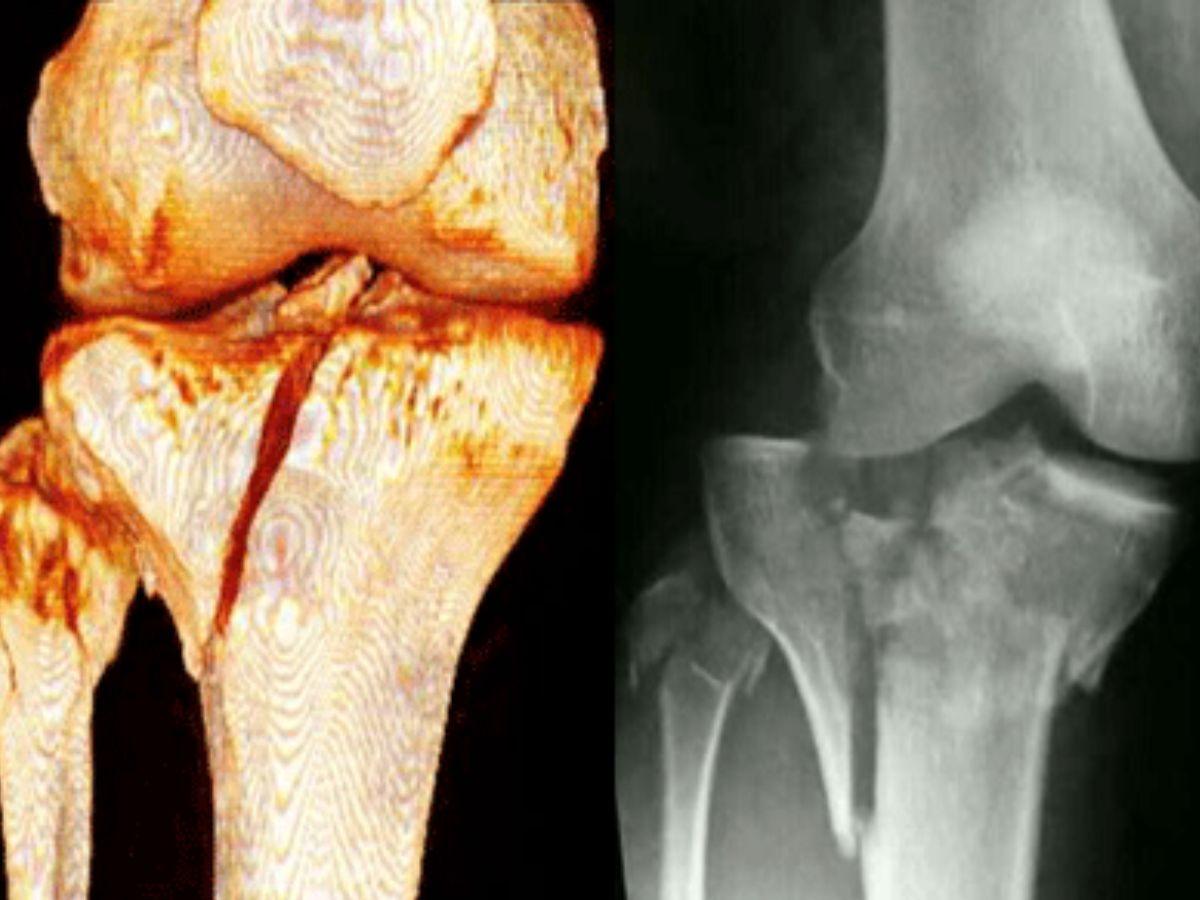

Gãy xương vùng khớp gối

Gãy xương khớp gối là tình trạng xương chày, xương mác, xương đùi hoặc xương bánh chè bị nứt hoặc vỡ do tai nạn hoặc va chạm mạnh đột ngột. Triệu chứng ban đầu của gãy xương khớp gối là cảm giác đau dữ dội ngay sau va chạm, sưng vù biến dạng, khó cử động và chèn ép dây thần kinh, gây nguy hiểm nghiêm trọng đến sức khỏe.

Gãy xương khớp gối (Nguồn: Thu Cúc)

Chẩn đoán hình ảnh: Để xác định chính xác tình trạng chấn thương, bác sĩ sẽ chỉ định thực hiện chẩn đoán hình ảnh như X-quang xác định gãy xương, chụp MRI, siêu âm để xác định mức độ thương tổn, nội soi khớp để xác định chấn thương khi không thể xác định.